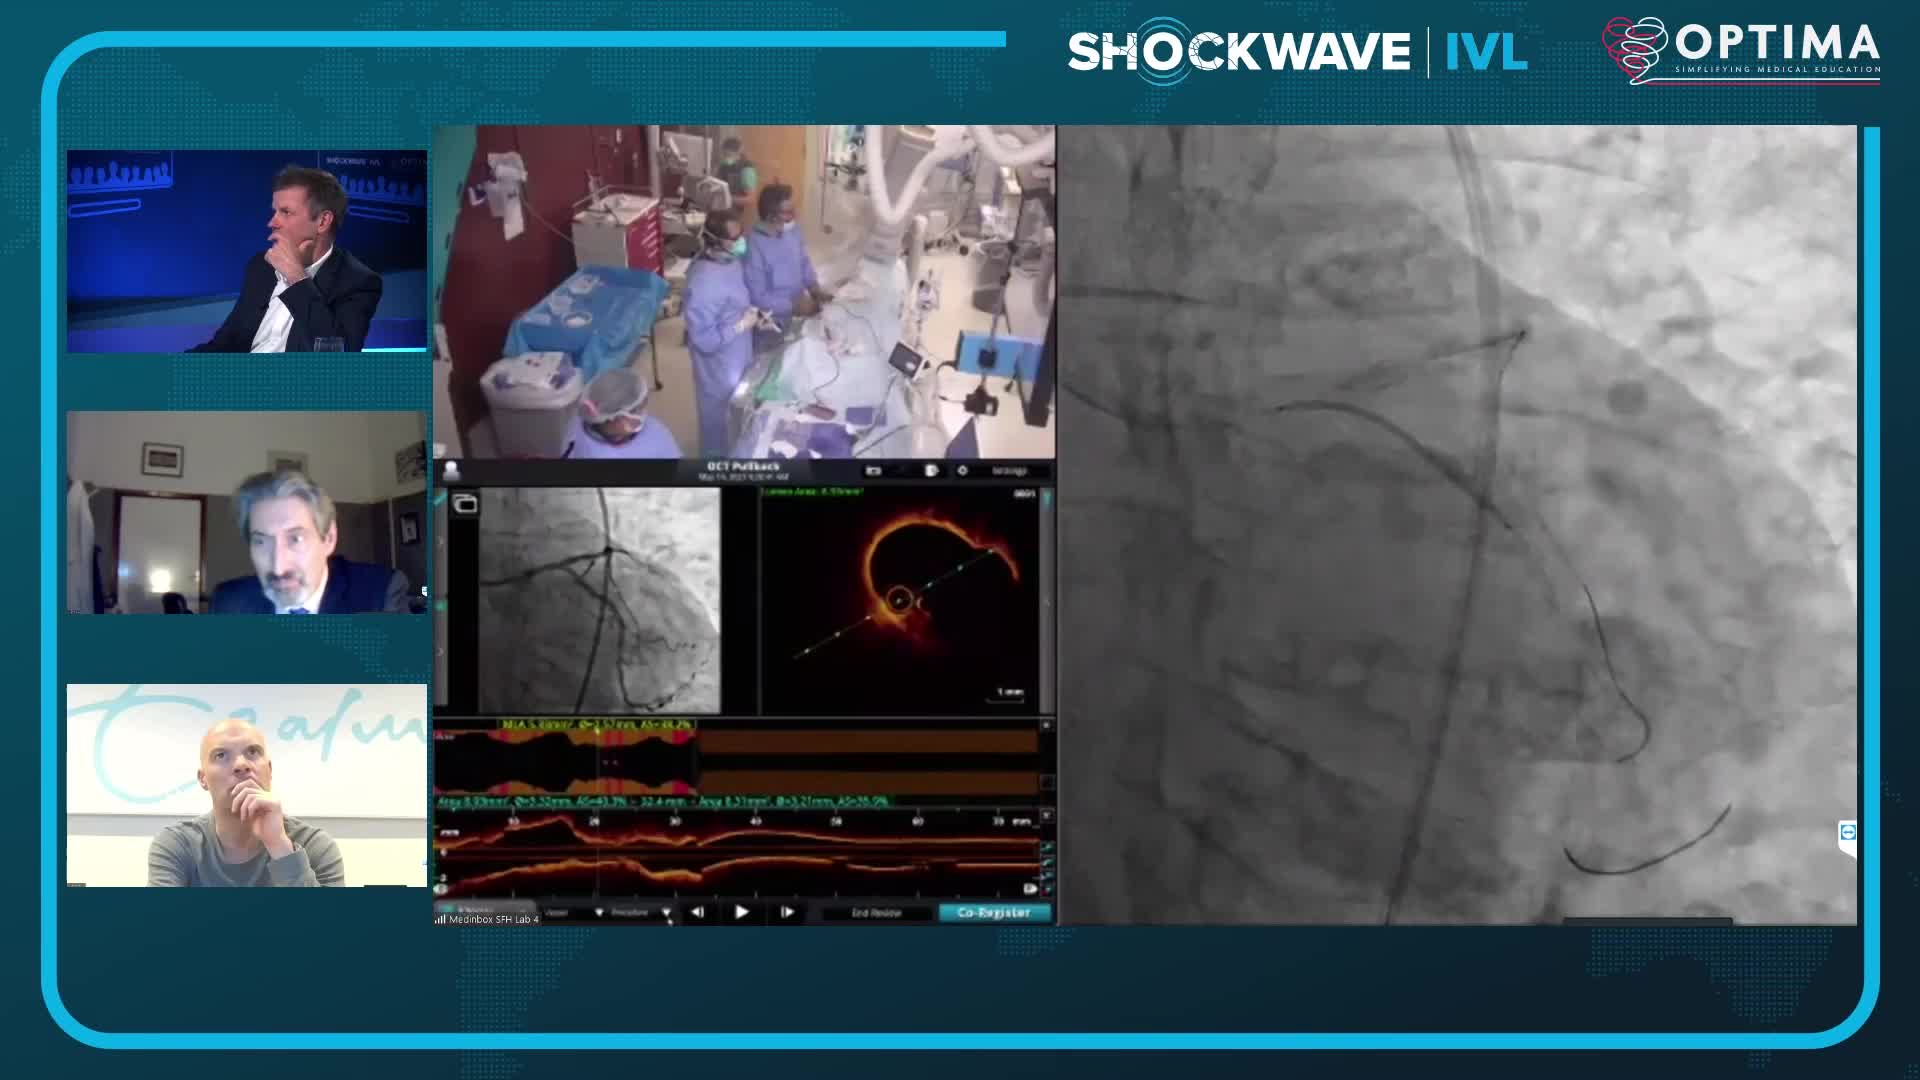

Calcium Masterclass with Shockwave IVL

Treatment of coronary arterial calcium (CAC) has being redefined. We explore the interaction between CAC and patient...